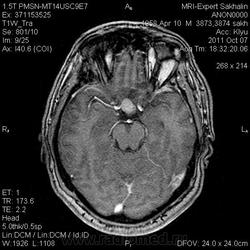

Аденома гипофиза

Вот такая аденома гипофиза сегодня.Мужчина с жалобами на снижение зрения.

постконтраст